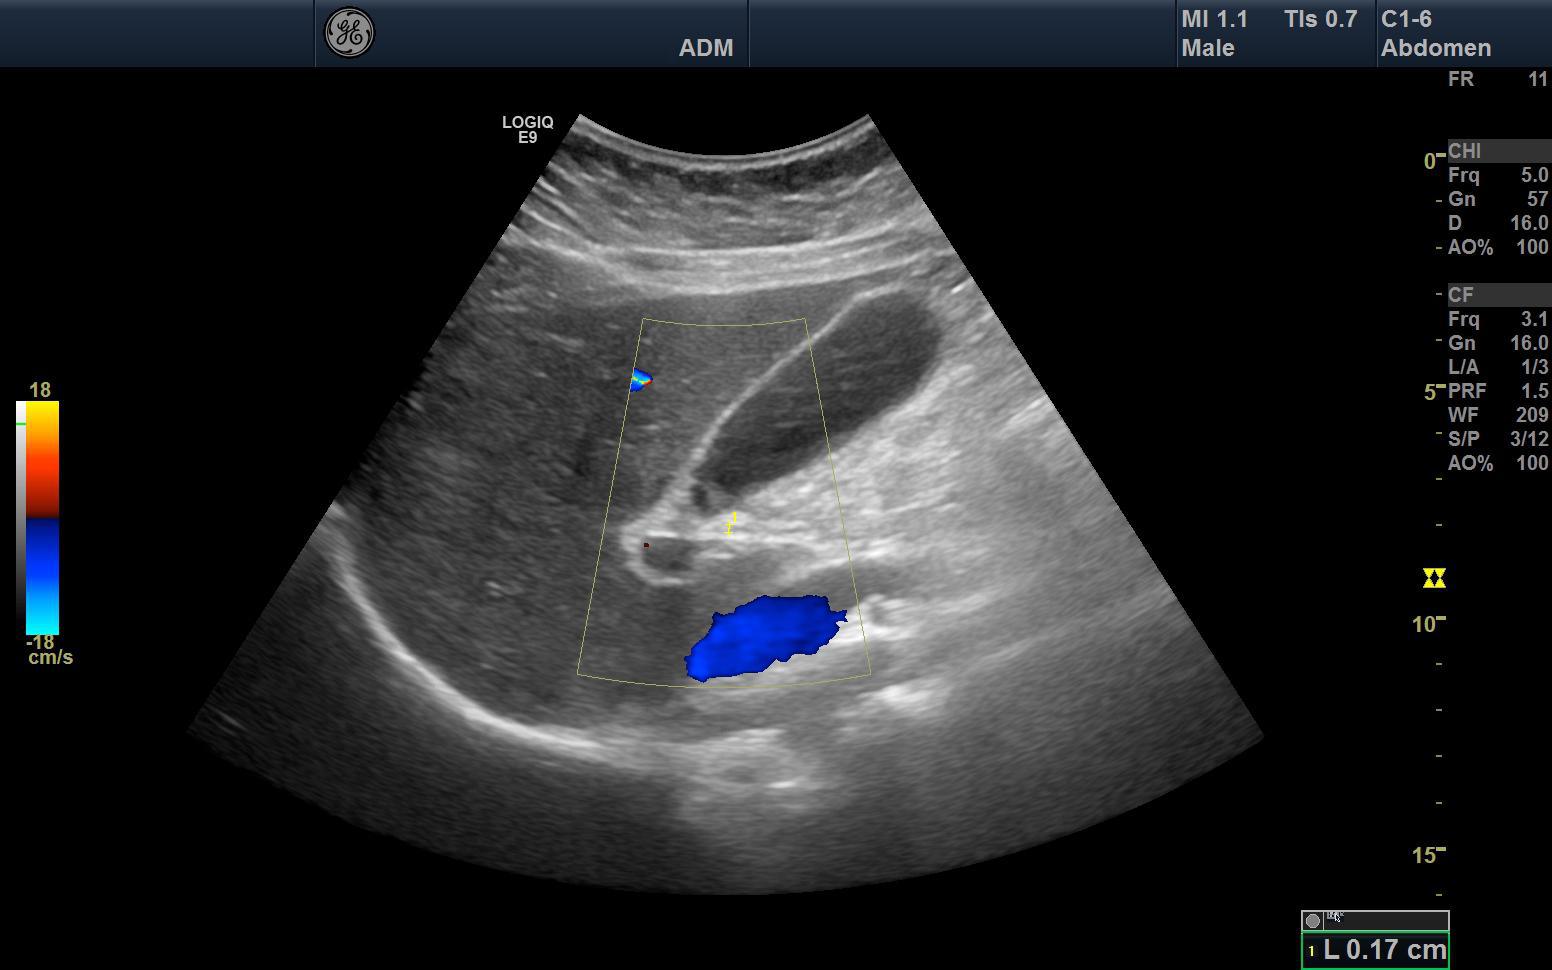

🧭 Fenêtres Acoustiques & Repères Anatomiques

L’examen débute souvent par la région sus-mésocolique, en utilisant le foie comme fenêtre acoustique principale.

Le parenchyme hépatique homogène permet d’identifier :

- La veine cave inférieure.

- Les veines sus-hépatiques.

- La vésicule biliaire.

💧 Recherche systématique du liquide libre :

- Espace hépato-rénal (de Morrison).

- Espace spléno-rénal.

- Récessus pelvien (cul-de-sac de Douglas chez la femme, vésico-rectal chez l’homme).

Le liquide libre apparaît anéchogène et suit toujours les espaces anatomiques déclives.